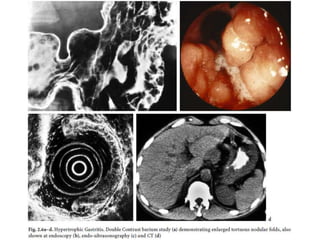

Hypertrophic gastritis

• Characterized

radiographically by

thickened folds, often

greater than 10 mm in

width, predominantly in the

fundus and body, which are

the acid-producing regions

of the stomach.

• The areae gastricae pattern

may be prominent, up to 4–

5 mm in size and more

angular and polygonal than

the usual round or oval

configuration

Hypertrophic gastritis in a patient with a recently healed lesser curvature

gastric ulcer. This characteristic enlargement and prominence of the areae

gastricae can be correlated with an increased incidence of gastric

hypersecretion and PUD